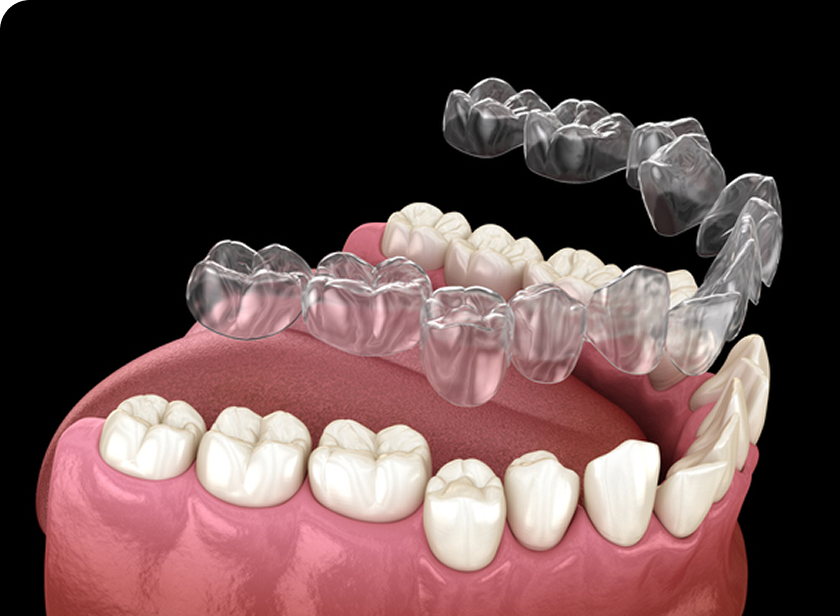

인비절라인(Invisalign)은 눈에 띄지않게 투명하게 제작된 교정 장치입니다.

치아 상태에 맞게 디지털 장비로 맞춤 설계된 투명 교정 장치를 주기적으로 교체하며 치아를 서서히 이동시키는 방식으로 진행됩니다.

기존의 금속 교정 장치와 달리 뛰어난 심미성으로

티나지 않는 교정을 원하시는 경우 적합하며 탈부착이 가능하여 위생관리가 편안합니다.

바른선택치과의원에서 사용하는 아이테로는 인비절라인치료를 위한 디지털 구강 스캐너로,

기존의 불편한 치아 본뜨기(인상 채득) 없이 3D 디지털 스캔으로 빠르고 정밀한 치아 상태 분석이 가능합니다.